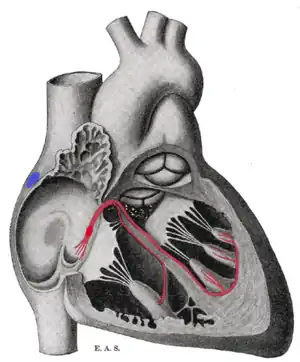

Isolated heart conduction system showing bundle of His | |

Heart cut-away showing the bundle of His. Schematic representation of the atrioventricular bundle of His. The bundle, represented in red, originates near the orifice of the coronary sinus, undergoes slight enlargement to form the AV node. The AV node tapers down into the bundle of His, which passes into the ventricular septum and divides into two bundle branches, the left and right bundles. Sometimes the 'left and right bundles of His' are called Purkyně or Purkinje fibers. The ultimate distribution cannot be completely shown in this diagram. | |